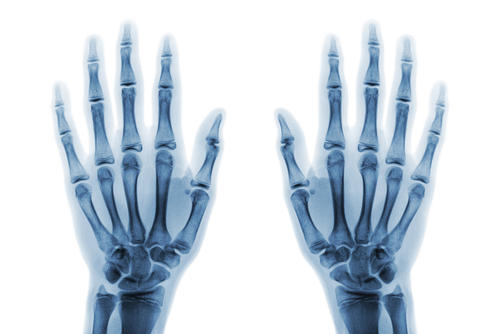

- Прямая проекция, при которой сканер направлен перпендикулярно к кисти – дает информацию о наиболее крупных костях;

- Боковая проекция, при которой сканер «смотрит» на боковое ребро ладони – дает информацию о более мелких костях, расположенных на периферии конечности;

- Косая проекция, при которой сканер выставлен под углом к ладони – позволяет визуализировать костные структуры в центральной части кисти.